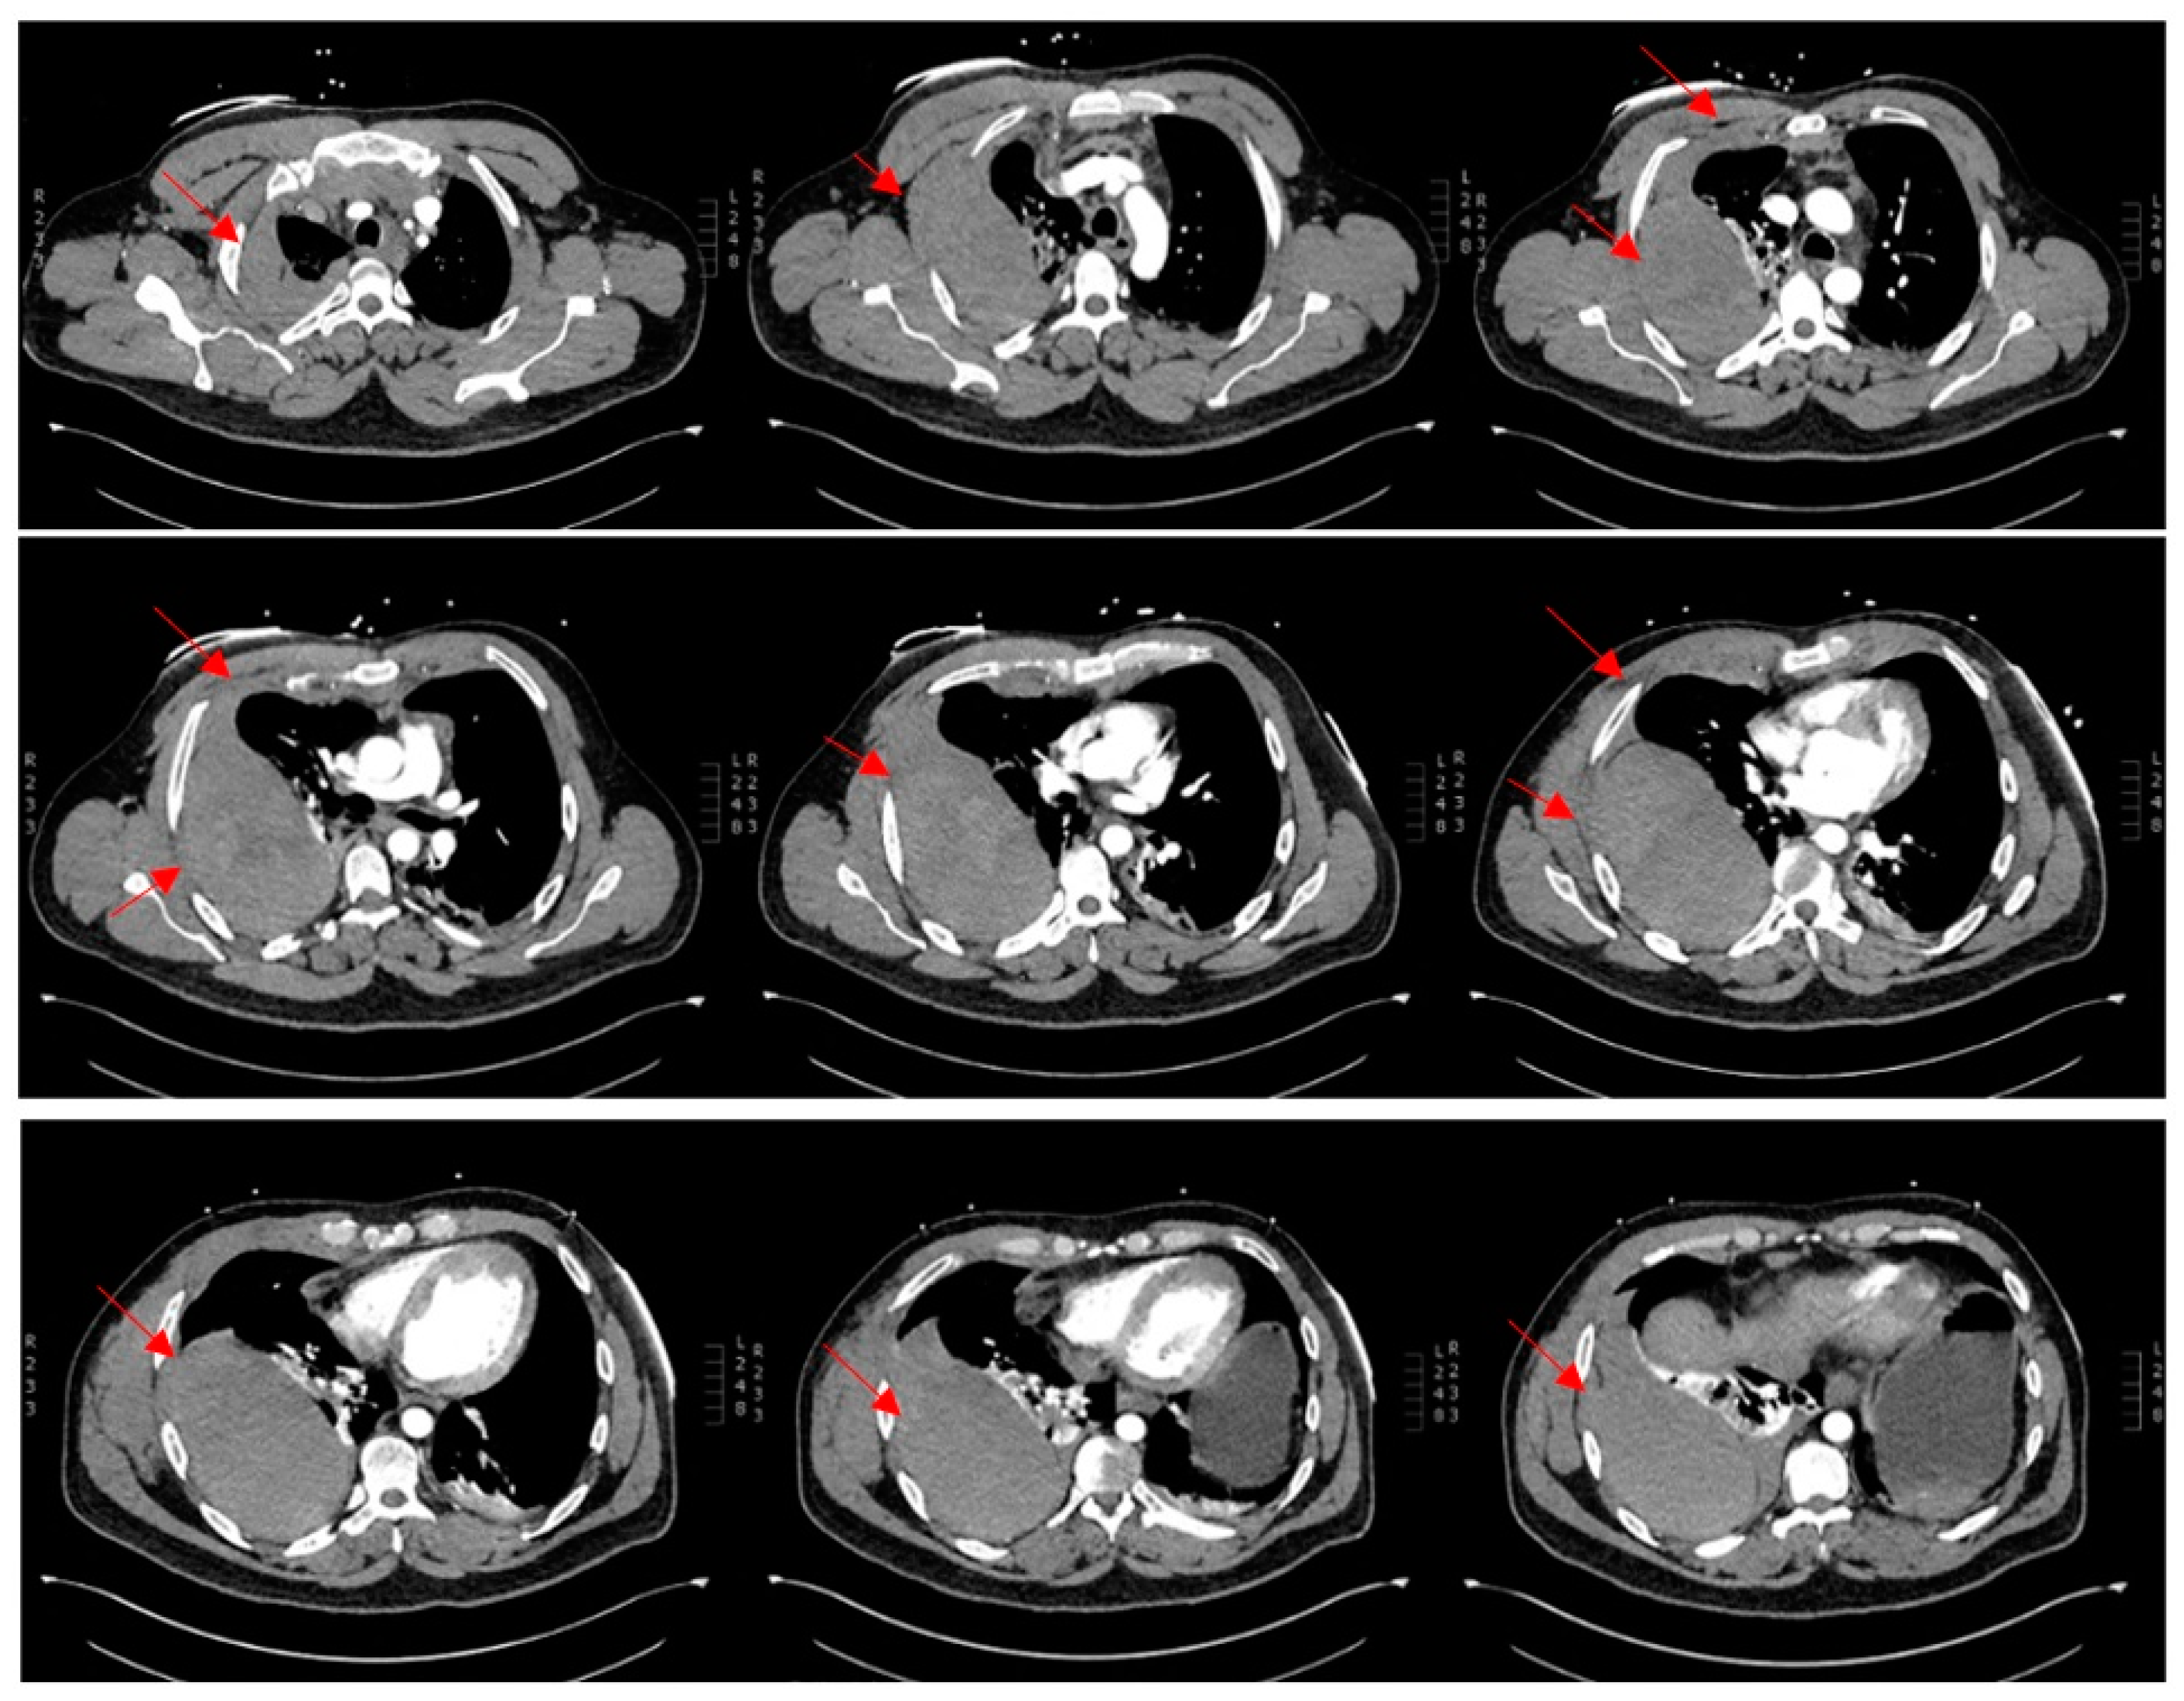

Acutely post-procedure, he complained of a right-sided apical pleuritic chest pain. At this time, his Glasgow coma scale was 15, he was afebrile, with a blood pressure of 132/81 mmHg, pulse rate of 72 bpm, tachypneic at 22 respirations per minute with 94% saturation on room air, and he had bilateral crepitations in his middle to lower zones. A chest X-ray (CXR) was performed immediately; the findings and radiograph are shown in Figure 1. A computed tomography (CT) scan with contrast of his chest was performed shortly after; the images and findings are shown in Figure 2. The concern for the hemothorax was increasing given the active bleed, and that the DAPT should not be stopped under any circumstance, due to high risk of stent thrombosis. A general surgical consult was sought which culminated in the recommendation of a cardiothoracic consult. Throughout this period, regular blood was taken to monitor the hemoglobin levels and for a blood group and matching.

Figure 2. Multiphase CT scan with contrast of chest progressing from superior to inferior. Multiple bilateral rib fractures of 2nd to 6th ribs bilaterally. Moderate right-sided hematoma seen in posterior right extra-pleural space with contrast extravasation seen at the posterior right 3rd and 4th intercostal space suggestive of an active bleed. Right hemothorax. Anterosuperior mediastinal hemoatoma. Collapse consolidation in lung bases. Ground glass opacities with smooth septal thickening in both lung apices. Abdominal organs (not shown) are unremarkable.